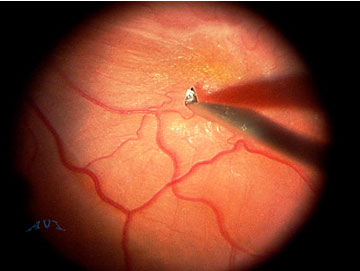

Images featured on this website were captured with A.V.I. Video Adapter and are the sole property of Advanced Visual Instruments, Inc. All retinal images were captured through A.V.I. Stereo Inverter and A.V.I. Panoramic Lenses. All images owe their superb quality of anatomical detail to the unique design and fine optics of A.V.I. products. To facilitate web viewing the images had been reduced in size.